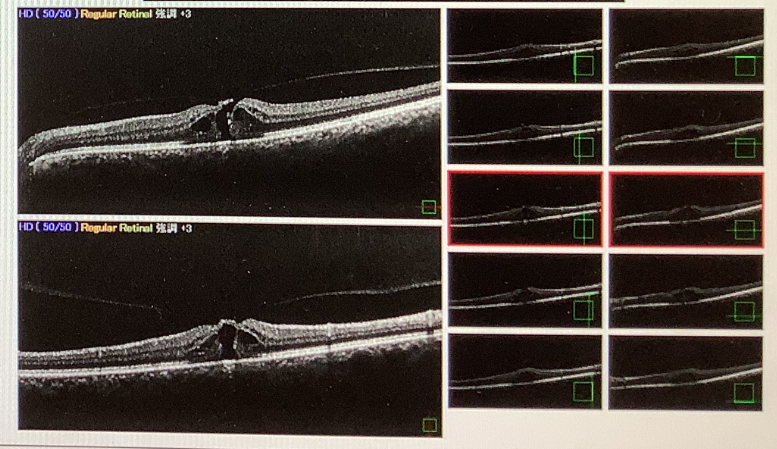

術後1.2あった視力は0.3まで低下し、左眼の中をみると、黄斑部に穴が開いている“黄斑円孔“という状態でした。歪みを生じる病気はいくつかあり、急を要さないものもありますが、この黄斑円孔はあまり放っておくとよくない病気です。治療としては手術(硝子体手術)が必要になりますが、時間が経ち過ぎてしまうと、手術で穴がきれいに塞がっても視力の改善が乏しいこともあります。なので、準緊急的に来週、手術を予定させていただきました。